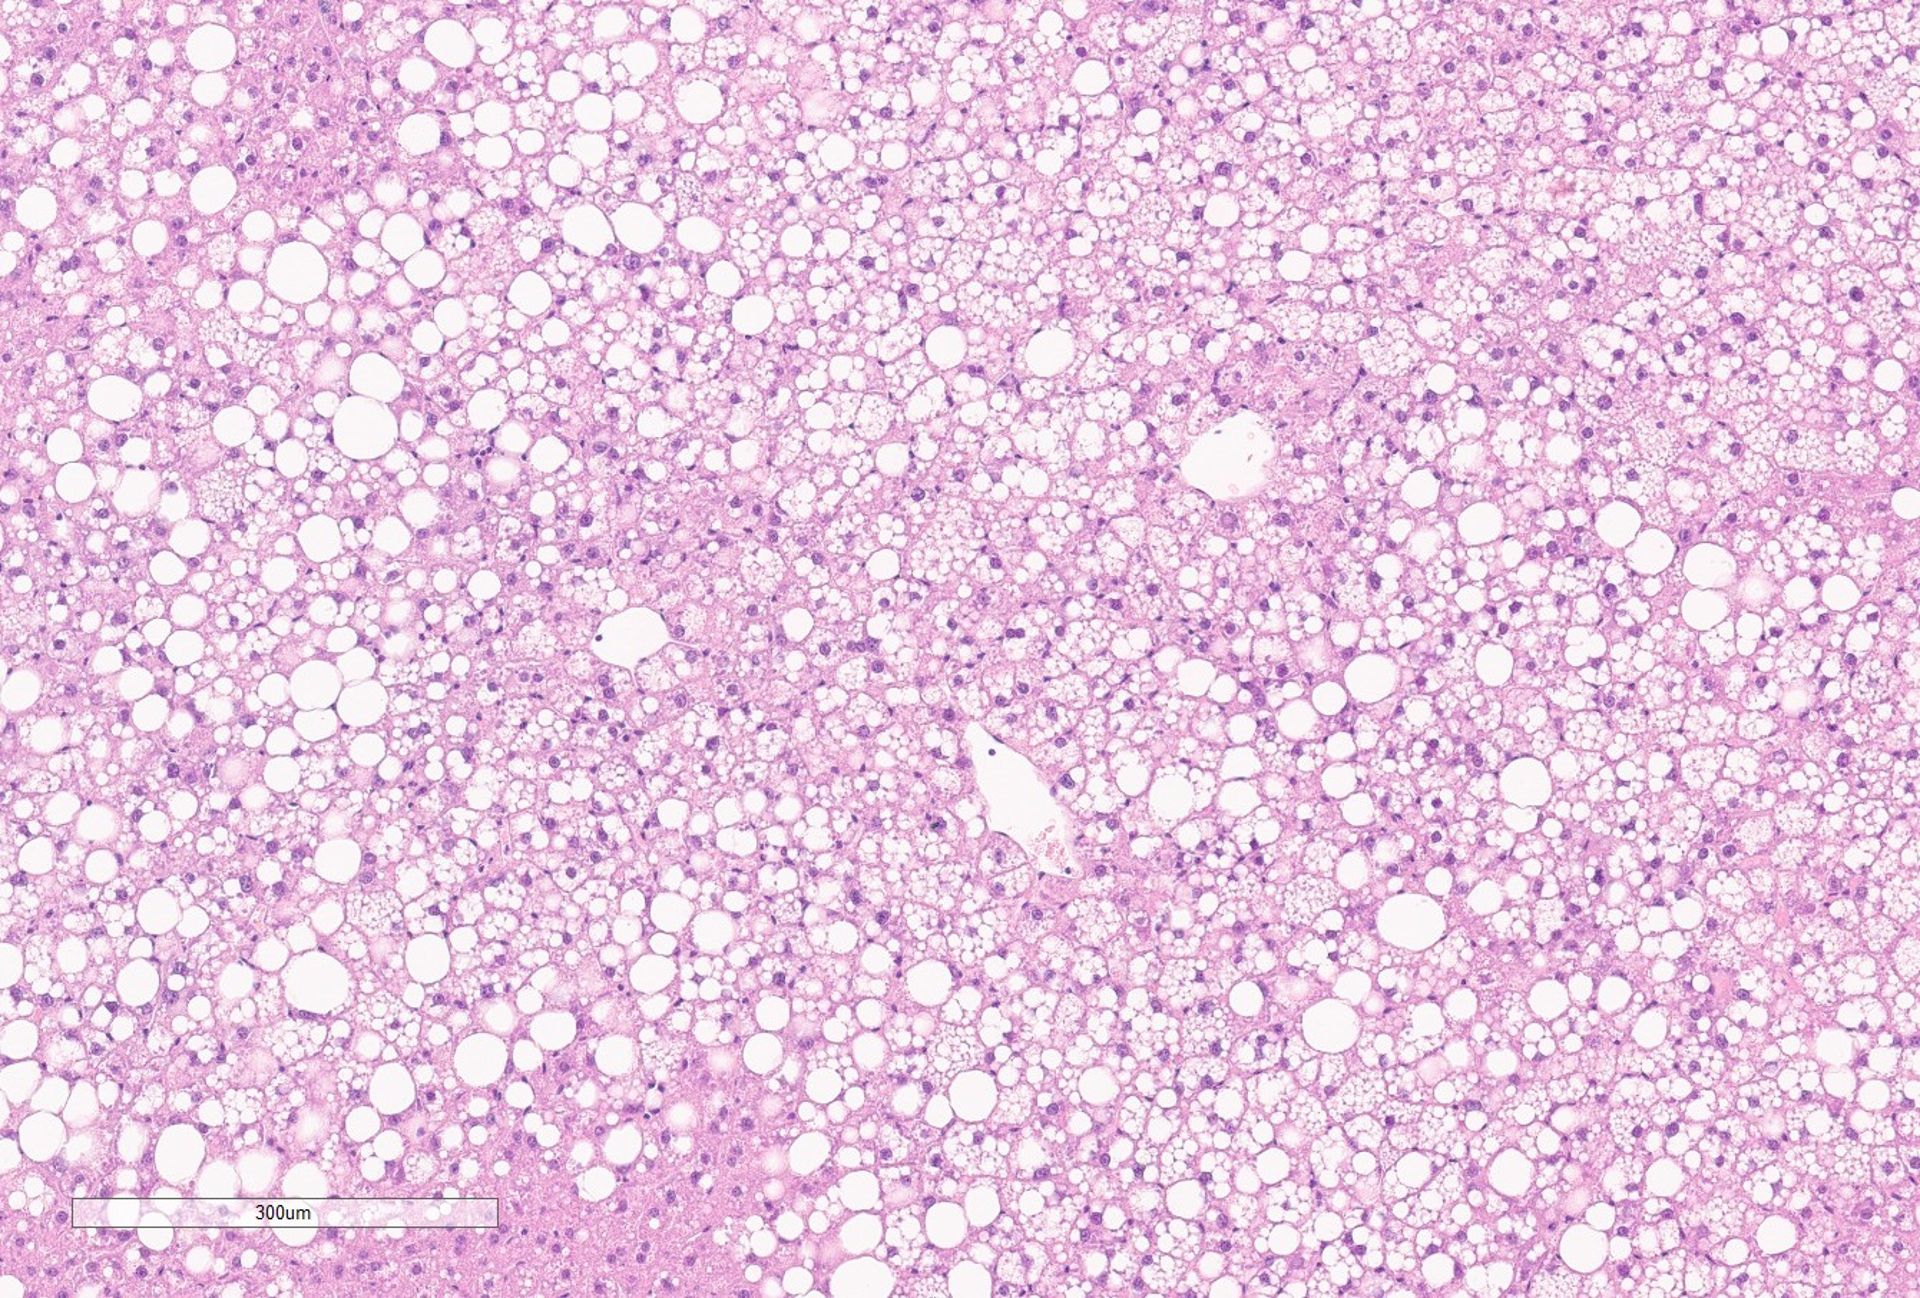

Leptin receptor deficiency (LEPRD) is a congenital genetic disease in which the brain no longer regulates appetite and energy balance signals.

This leads to hyperphagia (excessive eating), elevated blood glucose levels, and increased insulin resistance, resulting in a very severe form of pediatric obesity.

Dr. Laura Silvestri’s project aims to develop therapeutic strategies based on antisense oligonucleotides targeting a key regulatory pathway of liver metabolism.

Thanks to data recently generated by my group, we have shown that activation of the BMP-SMAD signaling pathway through liver-targeted antisense oligonucleotides is sufficient to improve lipid and sugar metabolism. By combining targeted gene modulation and appetite regulation, we aim to correct the metabolic defect underlying LEPRD.The goal is not only to intervene in this specific condition, but also to extend the approach to other forms of genetic obesity and rare metabolic disorders.